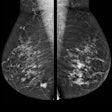

Hologic is a leading developer, manufacturer, and supplier of premium diagnostics, medical imaging systems, and surgical products dedicated to serving the healthcare needs of women.